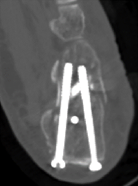

术后影像显示螺钉位置良好

常规切开复位内固定术创伤大、复位不准确,存在慢性疼痛、皮肤坏死、足踝活动受限、创伤性关节炎等风险。于是,骨科在中心主任吴超带领下,采用第三代天玑骨科手术机器人为程某开展跟骨微创内固定手术,该手术时间短、透视少、实现了精准复位和螺钉固定;术后影像显示螺钉位置良好,患者关节面恢复。